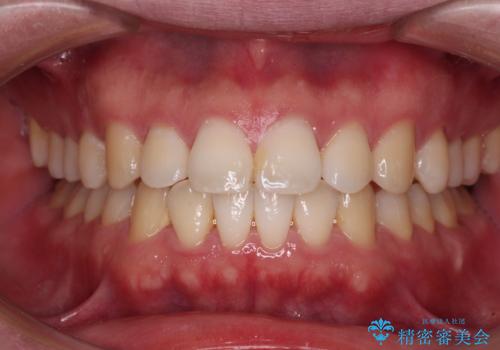

インビザラインで奥歯の咬み合わせと前歯のデコボコを改善

- 前歯のデコボコと奥歯の咬み合わせを気にして来院された患者様です。

前歯のデコボコはインビザラインで十分に対応可能と判断できましたが、咬合力が強いため、臼歯(特に右側)の交叉咬合はインビザライン単体では困難と思われました。

まずはインビザライン単体で矯正治療を開始し、交叉咬合が改善されない場合にはアンカースクリューなどの使用を検討することとしました。

インビザライン単体では右側の交叉咬合を解消することができなかったため、アンカースクリューを併用して咬合を改善させました。